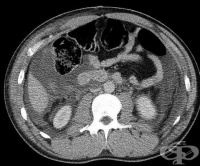

S35.4 Травма на бъбречните кръвоносни съдове

Травма на бъбречните кръвоносни съдове обхваща 16% от всички коремни съдови наранявания. 1,3 - 1,6 п...